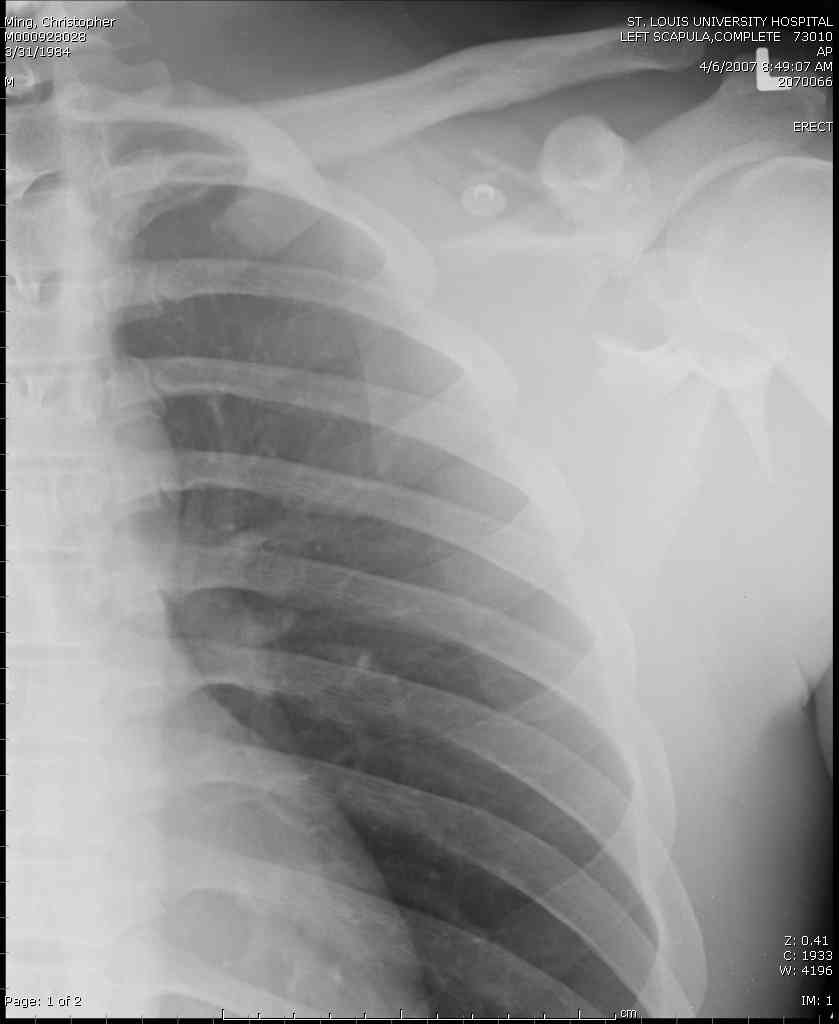

Для решения насчет оперативного вмещательства на лопатке сперва надо определиться с обьязательными ренгенологическими исследованиями, не менее трех стандартных проекций: прямая, аксиллярная и в позиции виде “Y”.

Прямую снимают под углом в 35 градусов от центра и вид “Y” в 90 градусов к нему. Несмотря на неудобства, больному необходимо сделать

аксиллярный снимок.

К-томографические и Трехмерные(3D)снимки крайне важны для определения внутрисуставных переломов и классификации.